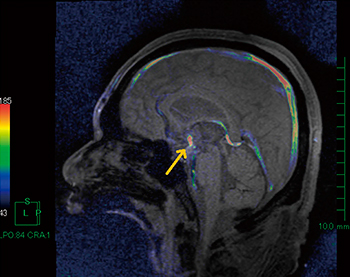

非交通性水頭症例における第三脳室底開窓術(EVT)の,手術前後での脳脊髄液のフローの確認に用いる。通常のフェーズコントラスト画像のシネ表示でも脳脊髄液のフローの確認はできるが,マグニチュード画像をカラー化してリフェーズ画像とフュージョンすることで,より明瞭にフローの存在部位や程度を確認することができる(図4)。

図4 水頭症フェーズコントラストフュージョンイメージ

第三脳室底開窓術後のフローなどをカラー化してシネ表示する。